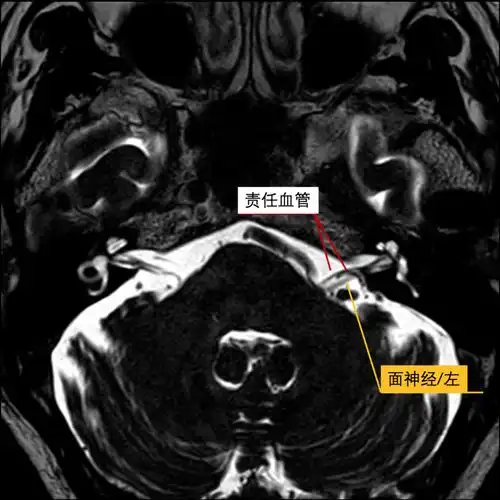

三叉神经痛,面肌痉挛手术前的主要影像学检查

术中图像术中充分分离面神经上方责任血管,并予teflon棉垫离减压.